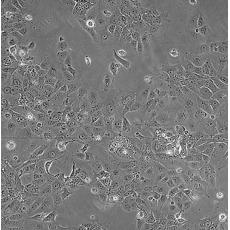

HCC827

產品名稱 HCC827

中文名稱 人非小細胞肺癌細胞

組織來源 肺腺癌;女性

細胞種屬 Homo sapiens, human

生長特性 adherent

培養基 RPMI-1640+10% FBS+1% P/S

形態特征 epithelial

細胞描述 This lung adenocarcinoma has an acquired mutation in the EGFR tyrosine kinase domain(E746-A750 deletion).